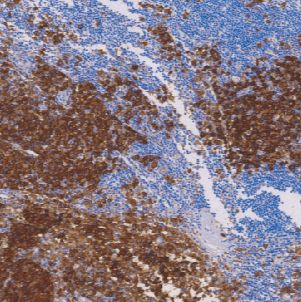

CD63广泛表达于造血和非造血细胞,诸如: 汗腺、Langerhan's岛、垂体、胰腺、支气管周腺体、潘氏细胞和前列腺等细胞中。单核细胞、巨噬细胞、活化的血小板等。CD63作为一种肿瘤抑制基因在恶性黑色素瘤中表达,对其扩散和转移起抑制作用。主要用于恶性黑色素瘤的诊断,但常与NCL-MelanA、NCL-TYROS、NCL-MIFE和NCL-S100p同时检测,以提高准确率。

- 阳性部位:胞膜

- 适用组织:石蜡切片

- 预处理:热修复